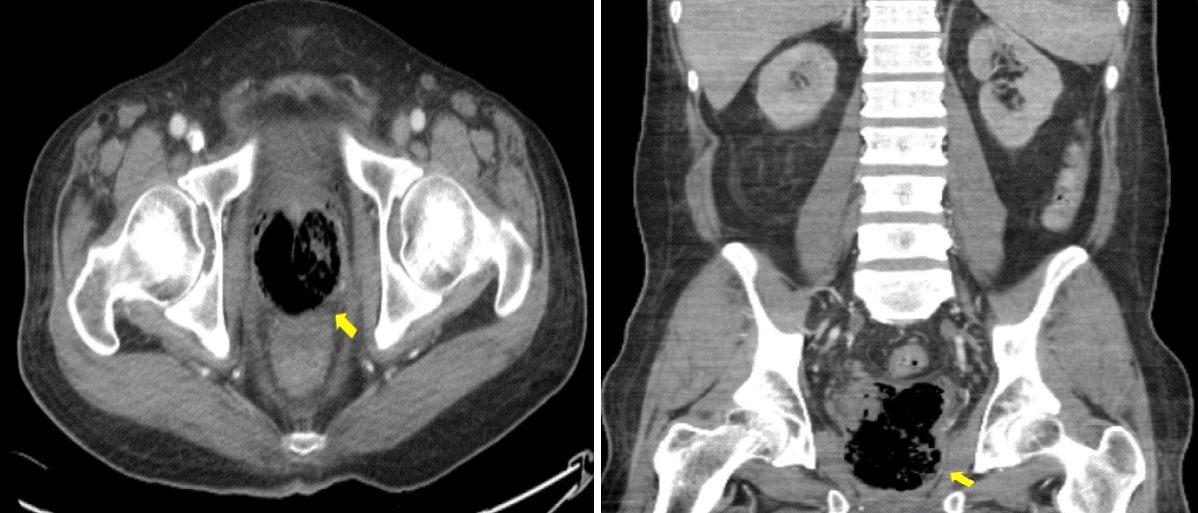

The patient was transferred to the intensive care unit (ICU) for further management as his septic shock worsened and respiratory compensation for metabolic acidosis was inadequate. Upon arrival in the ICU, he was intubated and placed on mechanical ventilation. Due to the apparent lack of infection control, a broader antibiotic regimen, specifically meropenem, was initiated. In addition, treatment with a polymyxin B-immobilized hemoperfusion filter (PMX-HP) was started for endotoxin removal, along with continuous renal replacement therapy (CRRT). An emergency urethral indwelling catheter was inserted to manage the retained urine and ongoing hematuria resulting from thrombocytopenia. One week later, the patient began to recover from septic shock and was successfully weaned off CRRT. Initial blood cultures had isolated extended-spectrum beta-lactamase negative Klebsiella pneumoniae; however, the antibiotic regimen was maintained due to the patient’s severe septic condition. In the second week of admission, the patient underwent a suprapubic cystostomy and removal of the indwelling catheter for urinary diversion. On hospital day 18, he was successfully extubated. A follow-up abdominal CT scan showed that the prostate gland was replaced with an abscess, indicated by a peripheral enhancing low-attenuation lesion with a maximum diameter (Dmax) of 8.2 cm in the coronal plane (Fig. 3).

Figure 3.

Follow-up CT imaging shows a 5.8 × 5.8 cm peripheral lesion with low attenuation in the prostate gland (arrows), suggesting the persistence of the prostate abscess. CT, computed tomography.